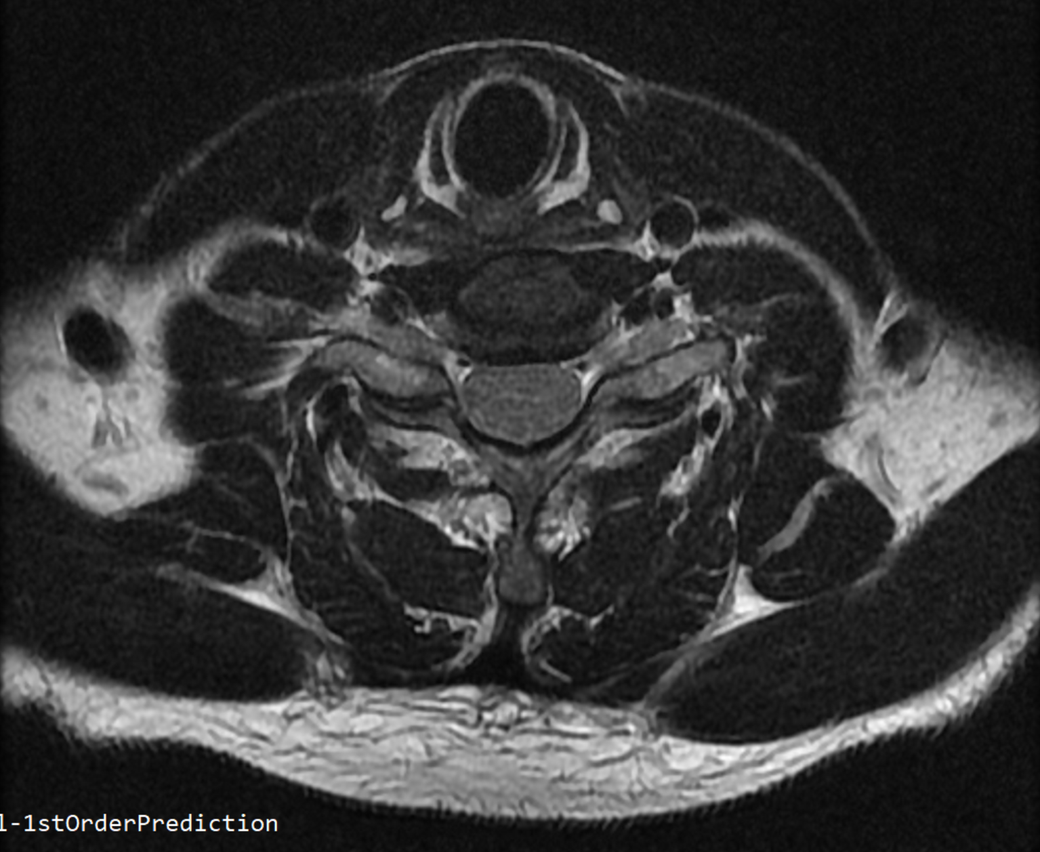

안녕하세요 목 경추 상단부터 순서대로 mri 촬영인데요

전체적으로 봐주시면 감사하겠습니다

하단8번 신경쪽도 나오는건지.. 봐주시면 감사하겠습니다

• 3번 째 사진